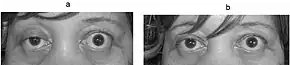

| Eye deviation and a drooping eyelid in a person with myasthenia gravis trying to open her eyes | |

In about two-thirds of individuals, the initial symptom of MG is related to the muscles around the eye.[11] There may be eyelid drooping (ptosis due to weakness of levator palpebrae superioris)[14] and double vision (diplopia,[11] due to weakness of the extraocular muscles).[12] Eye symptoms tend to get worse when watching television, reading, or driving, particularly in bright conditions.[11] Consequently, some affected individuals choose to wear sunglasses.[11] The term "ocular myasthenia gravis" describes a subtype of MG where muscle weakness is confined to the eyes, i.e. extraocular muscles, levator palpebrae superioris, and orbicularis oculi.[14] Typically, this subtype evolves into generalized MG, usually after a few years.[14]